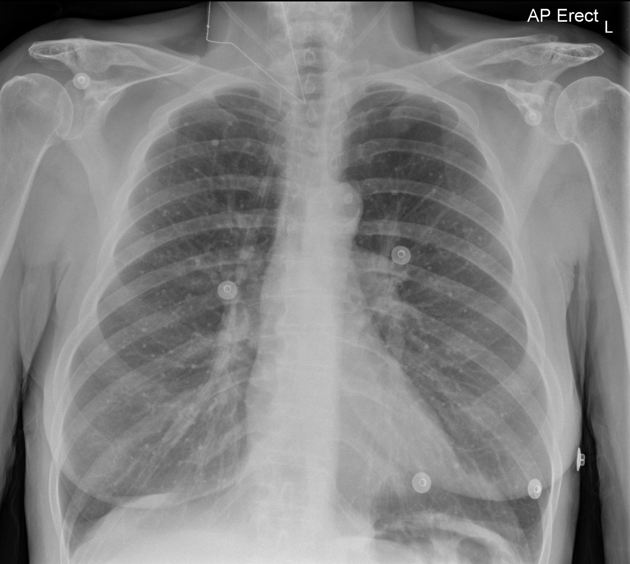

CXR: Interstial Lung Disease DDx

Lymphangitic Carcinomatosis:

Usually arises from adenocarcinomas such as:

Findings:

DDx: (these are also for interlobar septal thickening)